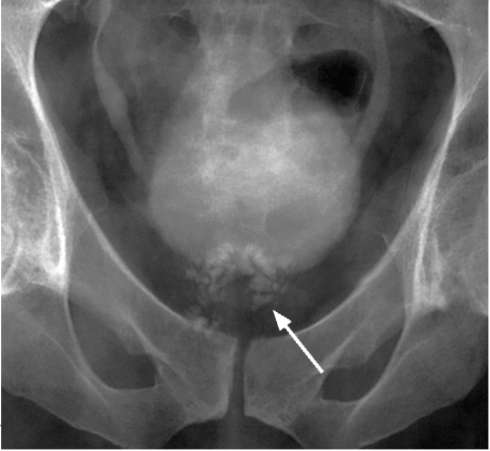

На обзорной рентгенограмме мочевых путей в проекции предстательной железы могут определяться тени обызвествленных участков с нечеткими, изъеденными контурами (рис. 10.5).

Рис. 10.5. Нисходящая цистограмма. Кавернозная форма туберкулеза предстательной железы (стрелка)